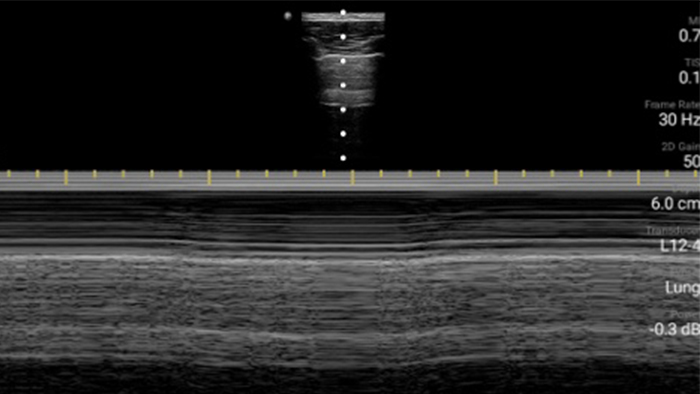

Exceptional ultrasound imaging

Lumify handheld ultrasound offers images that enhance diagnostic confidence.

See more when it counts

Lumify can help you make real-time decisions with more confidence, from assessment to recovery. Reveal the subtle details of an image, uncover enriched tissue definition with multiple angles and much more.